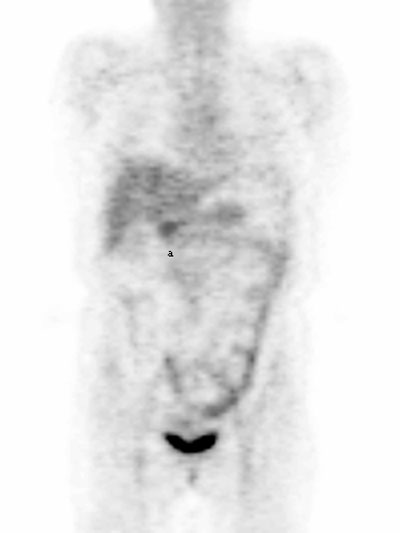

Fig. 18. - Imagen coronal de tomografía por emisión de positrones de cuerpo completo. Varón de 40 años sin antecedentes personales. Se aprecia la eliminación fisiológica de la [18]FDG en cálices y pelvis renales, ureteres y vejiga.